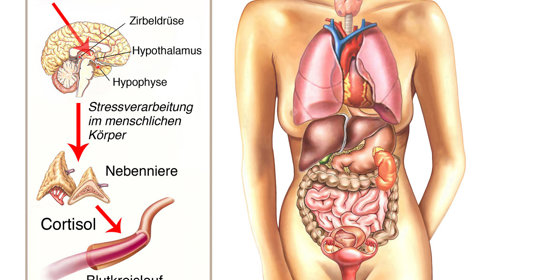

大腦與神經